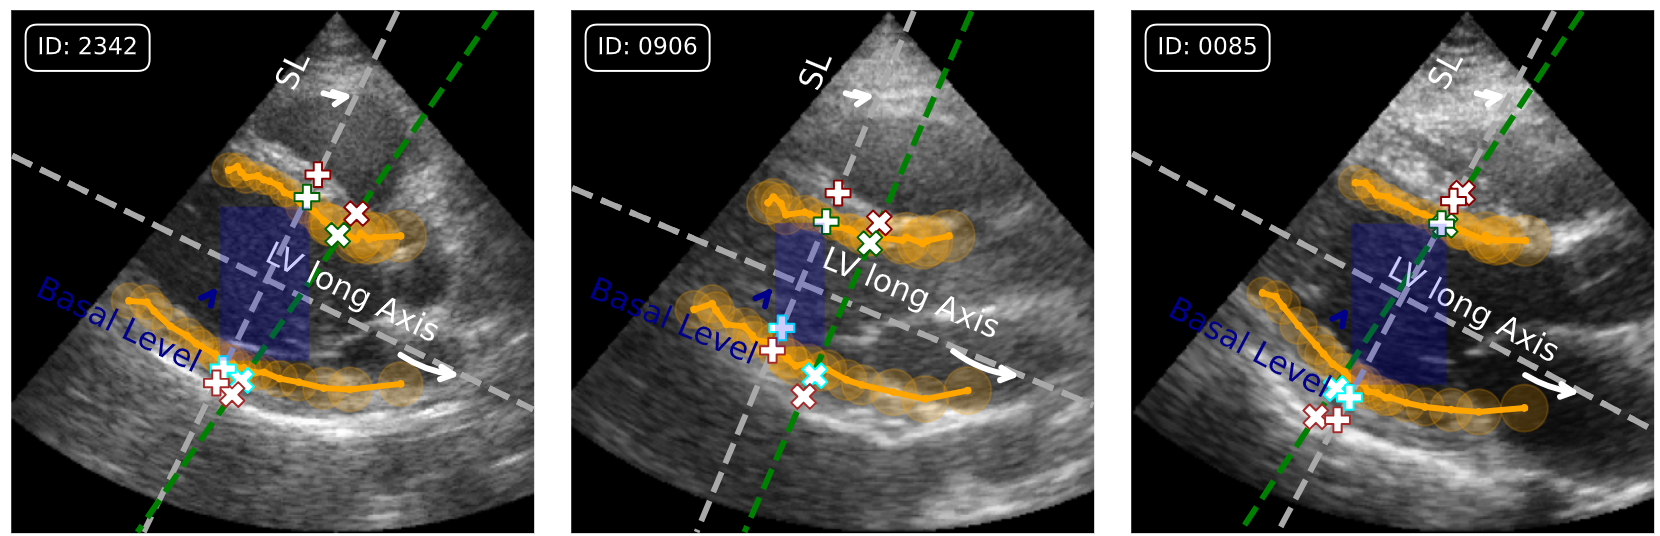

Figure 4: Visualization of Ground Truth (GT) and predicted landmarks with WiseLVAM. (X) denotes GT landmarks, + denotes predicted landmarks along the SL, with the predicted B-mode contour (orange) and basal level (blue). (Best viewed in color)

Visualization

Figure 4 illustrates the process of estimating LV linear measurements from B-mode images. The Wise model predicts the LV contour using NLV=20N_{\text{LV}}=20 landmark segments, identifies the basal level, and estimates the LV long axis. A virtual SL is then placed perpendicular to the estimated long axis, and EnLVAM is used to predict landmarks for automatic LV linear measurement.